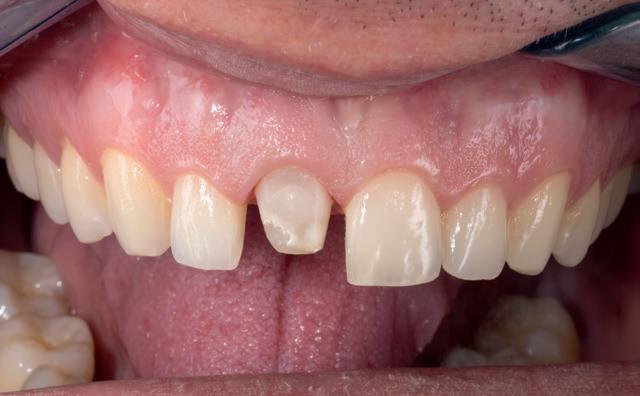

Case Study

Class IV controlled layer concept utilising G-ænial™ A’CHORD in 3 shades

This case study presents the clinical management of a patient who presented with an existing failed anterior composite, requiring a Class IV direct composite replacement. The restoration aimed to achieve seamless integration with the natural dentition while restoring form and function.

Figure 1 - Pre-Operative presentation, exhibiting a failed direct composite restoration on the upper left central incisor (Tooth 21).

Figure 7 – 2-week review demonstrating the complete optical and functional G-ænial™ A’CHORD restoration on the tooth 21.

Figure 2 - Tooth surface cleaned and prepared with 37% Phosphoric Acid Etch prior to application of the adhesive with G-Premio BOND.